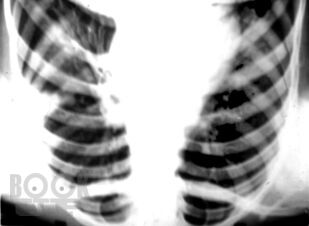

В руководстве для врачей излагаются вопросы истории становления противотуберкулезной службы в России, представлены сведения по микробиологии, эпидемиологии и фундаментальные данные во фтизиопульмонологии. Подробно рассмотрены клинические формы туберкулеза органов дыхания, синдромная диагностика и синдромная дифференциальная диагностика туберкулеза органов дыхания, вопросы саркоидоза в работе фтизиатра и терапевта. Обращено внимание на основные осложнения туберкулеза и оказание помощи при них, коморбидную патологию, современное этиопатогенетическое лечение больных туберкулезом, в том числе с использованием авторских индивидуальных методов активационной патогенетической терапии. Особое место в книге занимают вопросы профилактики и организации борьбы с эндемией туберкулеза. Руководство предназначено для врачейфтизиатров, рентгенологов, терапевтов и инфекционистов, а также для студентов высших медицинских учебных заведений по специальностям «Лечебное дело», «Педиатрия» и «Профилактическое дело».